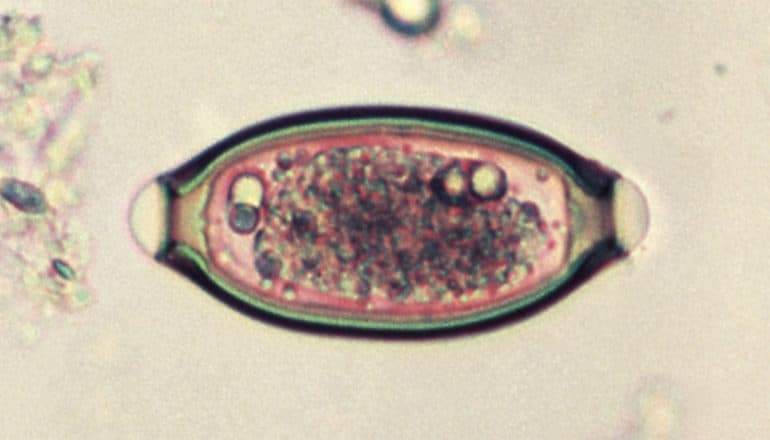

whipworm egg: oval capsule with tiny circles inside

Eggs, not worms, made it possible for researchers to examine the genetic material of thousands-of-years-old whipworms. Due to extremely durable chitin in egg capsules, their internal DNA has been well preserved while the eggs have been buried in moist soil.

By examining fossilized stool samples which were previously discovered in the latrines of Viking settlements in Viborg and Copenhagen, the researchers isolated the eggs under a microscope, sieved them from the stool, and subjected them to refined genetic analyses that the researchers have been perfecting for years in previous studies.

“We have known for a long time that we could detect parasite eggs up to 9,000 years old under a microscope. Lucky for us, the eggs are designed to survive in soil for long periods of time. Under optimal conditions, even the parasite’s genetic material can be preserved extremely well. And some of the oldest eggs that we’ve extracted some DNA from are 5,000 years old. It has been quite surprising to fully map the genome of 1,000-year-old well-preserved whipworm eggs in this new study,” explains Kapel.